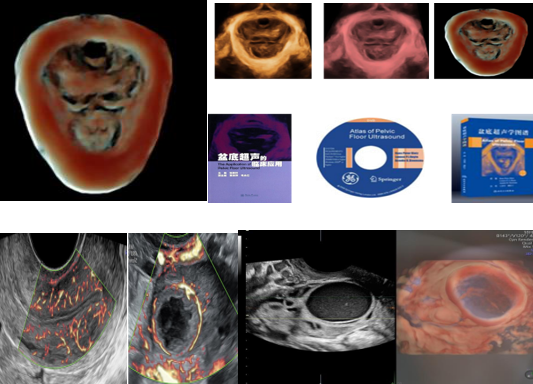

妇科领域

盆底三维四维超声有着多平面成像的优势,通过容积数据采集获得更清晰的图像,为临床诊断提供更丰富、有效的信息;妇科肿瘤方面,“煊流技术”提高了微小血管的敏感性,有助于肿瘤良恶性的鉴别诊断。